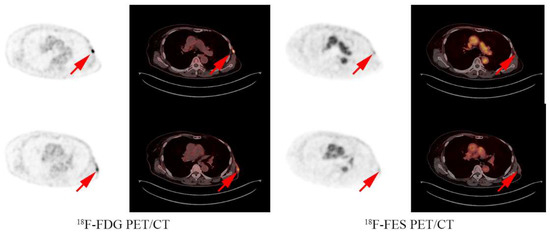

Figure 3.

Analysis examples: A 73 year old female had an FES positive lesion in the chest wall and a FES negative lesion in the axillary lymph nodes and received fulvestrant treatment with a PFS of 4 months.